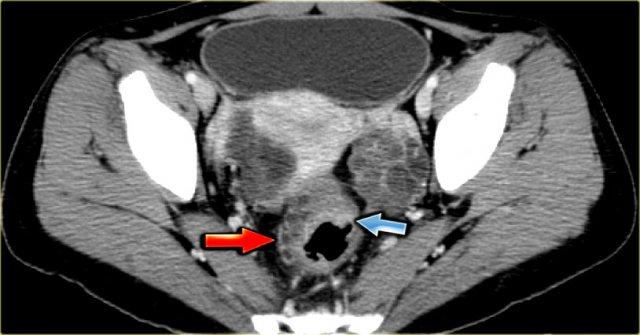

Trên siêu âm, cả hai buồng trứng đều to rõ rệt và chứa các thành phần nang với các thành phần đặc trong lòng nang (mũi tên).

Các tổn thương đặc-nang phức tạp, kết hợp với tính chất hai bên, rất nghi ngờ cho u nang buồng trứng thực sự và cần được đánh giá thêm.

CT của cùng bệnh nhân xác nhận các tổn thương đặc-nang phức tạp hai bên kích thước lớn, phồng vào ổ bụng.

Mục đích của CT không phải là xác nhận những gì đã biết từ siêu âm, mà là để phân giai đoạn bệnh.

Đối với bệnh nhân này, các đặc điểm quan trọng được thể hiện trên hình bên trái.

Có một tổn thương cấy ghép phúc mạc.

Khối u đã được phẫu thuật cắt bỏ và kết quả giải phẫu bệnh cho thấy đây là ung thư biểu mô buồng trứng dạng nội mạc tử cung.